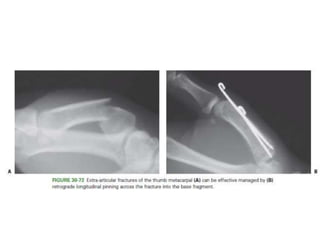

Carpometacarpal (CMC) Fractures

• The normal ROM at the thumb CMC joint

• 50 degrees of flexion-extension

• 40 degrees of abduction-adduction

• 15 degrees of pronation-supination.

Carpometacarpal (CMC) Fractures •The normal ROM at the thumb CMC joint • 50 degrees of flexion-extension • 40 degrees of abduction-adduction • 15 degrees of pronation-supination.

• #140 The distal metacarpal is adducted and supinated by the adductor pollicis. At the same time, the APL pulls the metacarpal radially and proximally.

• #143 (WAGNER) ■ Maintaining fracture reduction by manual traction and pressure, drill a 0.045- or 0.062-inch Kirschner wire into the base of the metacarpal across the joint and into the trapezium. Apply a forearm cast, holding the wrist in extension and the thumb in abduction; leave the thumb interphalangealjoint free.